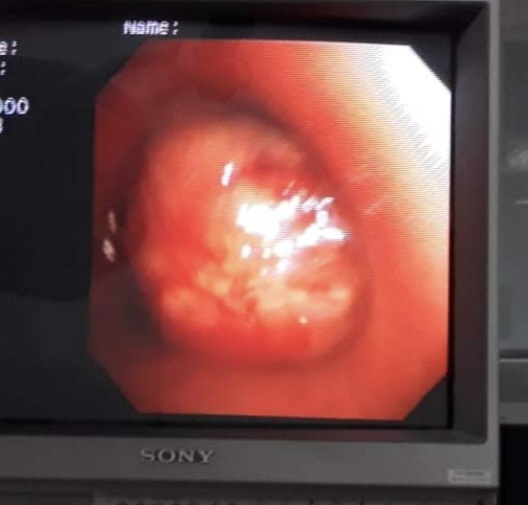

draurtecho Abr 6, 2026 La fibrobroncoscopia es una técnica que permite visualizar el interior de la tráquea y de los bronquios, y obtener muestras de éstos, para su análisis. A continuación unas imágenes de un tipo de cáncer de pulmón, visto por fibrobroncoscopia No Comments InNeumología